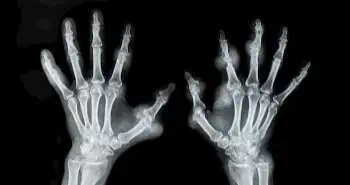

Abatacept found effective for RA patients as assessed by MRI of bilateral hands

Abatacept could be used to prevent bone destruction and may even allow repair of erosion as it significantly reduced synovitis and osteitis and prevented further decline of erosion and cartilage damage after 12 months of treatment.

A study recently revealed that abatacept treatment reduced synovitis and osteitis scores and did not worsen erosion and JSN scores at Month 12. Over 10% of patients experienced repair of erosion. Throughout the past few decades, various pharmacotherapies options like NSAIDs, corticosteroids, disease-modifying anti-rheumatic drugs (DMARDs) listed in RA management. One such drug which is proven very effective in RA treatment is Abatacept.

This study summarizes the evaluation of abatacept efficacy among 35 RA patients through magnetic resonance imaging (MRI) of bilateral hands. The MRI evaluation was done at baseline and after 12months of abatacept treatment. The MRI images which were taken into account for evaluation were erosion, synovitis, joint space narrowing (JSN) and osteitis. The RA MRI Scoring System (RAMRIS) was used to rank these images. The change in RAMRIS score was considered as the primary endpoint.  The repair of erosion also noticed after the treatment. This was the negative change in the erosion scores which were noticed higher than the smallest detectable changes (SDCs).

Out of 35 patients, 31 finished the treatment therapy. The osteitis and synovitis scores exhibited a great statistical decrease at 12th month. On the other hand, no changes were seen in  JSN and median erosion scores. Only 11% of participants exhibited repair of erosion & obtained a functional remission. However, 83% of participants reflected no change in erosion scores. The study evaluated the Simplified Disease Activity Index response rate in the first month of treatment as an independent factor which predicted changes in the erosion scores after 12-month treatment.